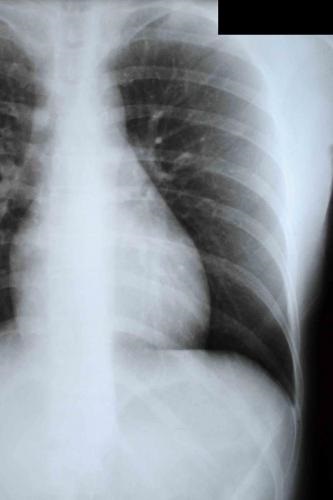

Az első X-ray végzett napján sérülés. Ez a fragmentum egy mellkasi síkfólia közvetlen vetítés (a jobb oldalon nem létezik):

Az első ok a „láthatatlanság” törések - ez egy rossz arány a helyét, és a vetítés röntgen. Bordatörés a hónalji vonalak, különösen a hónalj középvonalában a sima film közvetlen vetítésre be a területre, a vetítés impozáns árnyékok a bordák. Ezért vannak ilyen röntgenfelvétel nem látható és nem látható. Az első X-ray ilyen.

A jövőben a klinika tartottuk, nem röntgensugarak a ferde - a második és minden további röntgen. Megjegyzés: a penge, mert könnyű navigálni. Törések a hónalj középvonalában.

A második ok a „láthatatlanság” - kombinációja hiánya elmozdulását a csont fragmentumok, különösen akkor, ha nem teljes törések, a vetítés, amelyben a sugár útvonal nem esik egybe a törési síkra. Így miatt ugyanazt a vetítési átfedések különböző rétegeinek borda törés lehet ismét láthatatlan.

Hogy őszinte legyek, a második röntgenfelvétel Én miután néhány homályos kétséges, de határozottan megerősíti a törés a hetedik borda, én nem merem. A harmadik röntgenfelvétel kétség jelentősen megnövekedett. De a negyedik X-ray, amely tisztán látható, bőrkeményedés egyértelműen lezárja a kérdést.